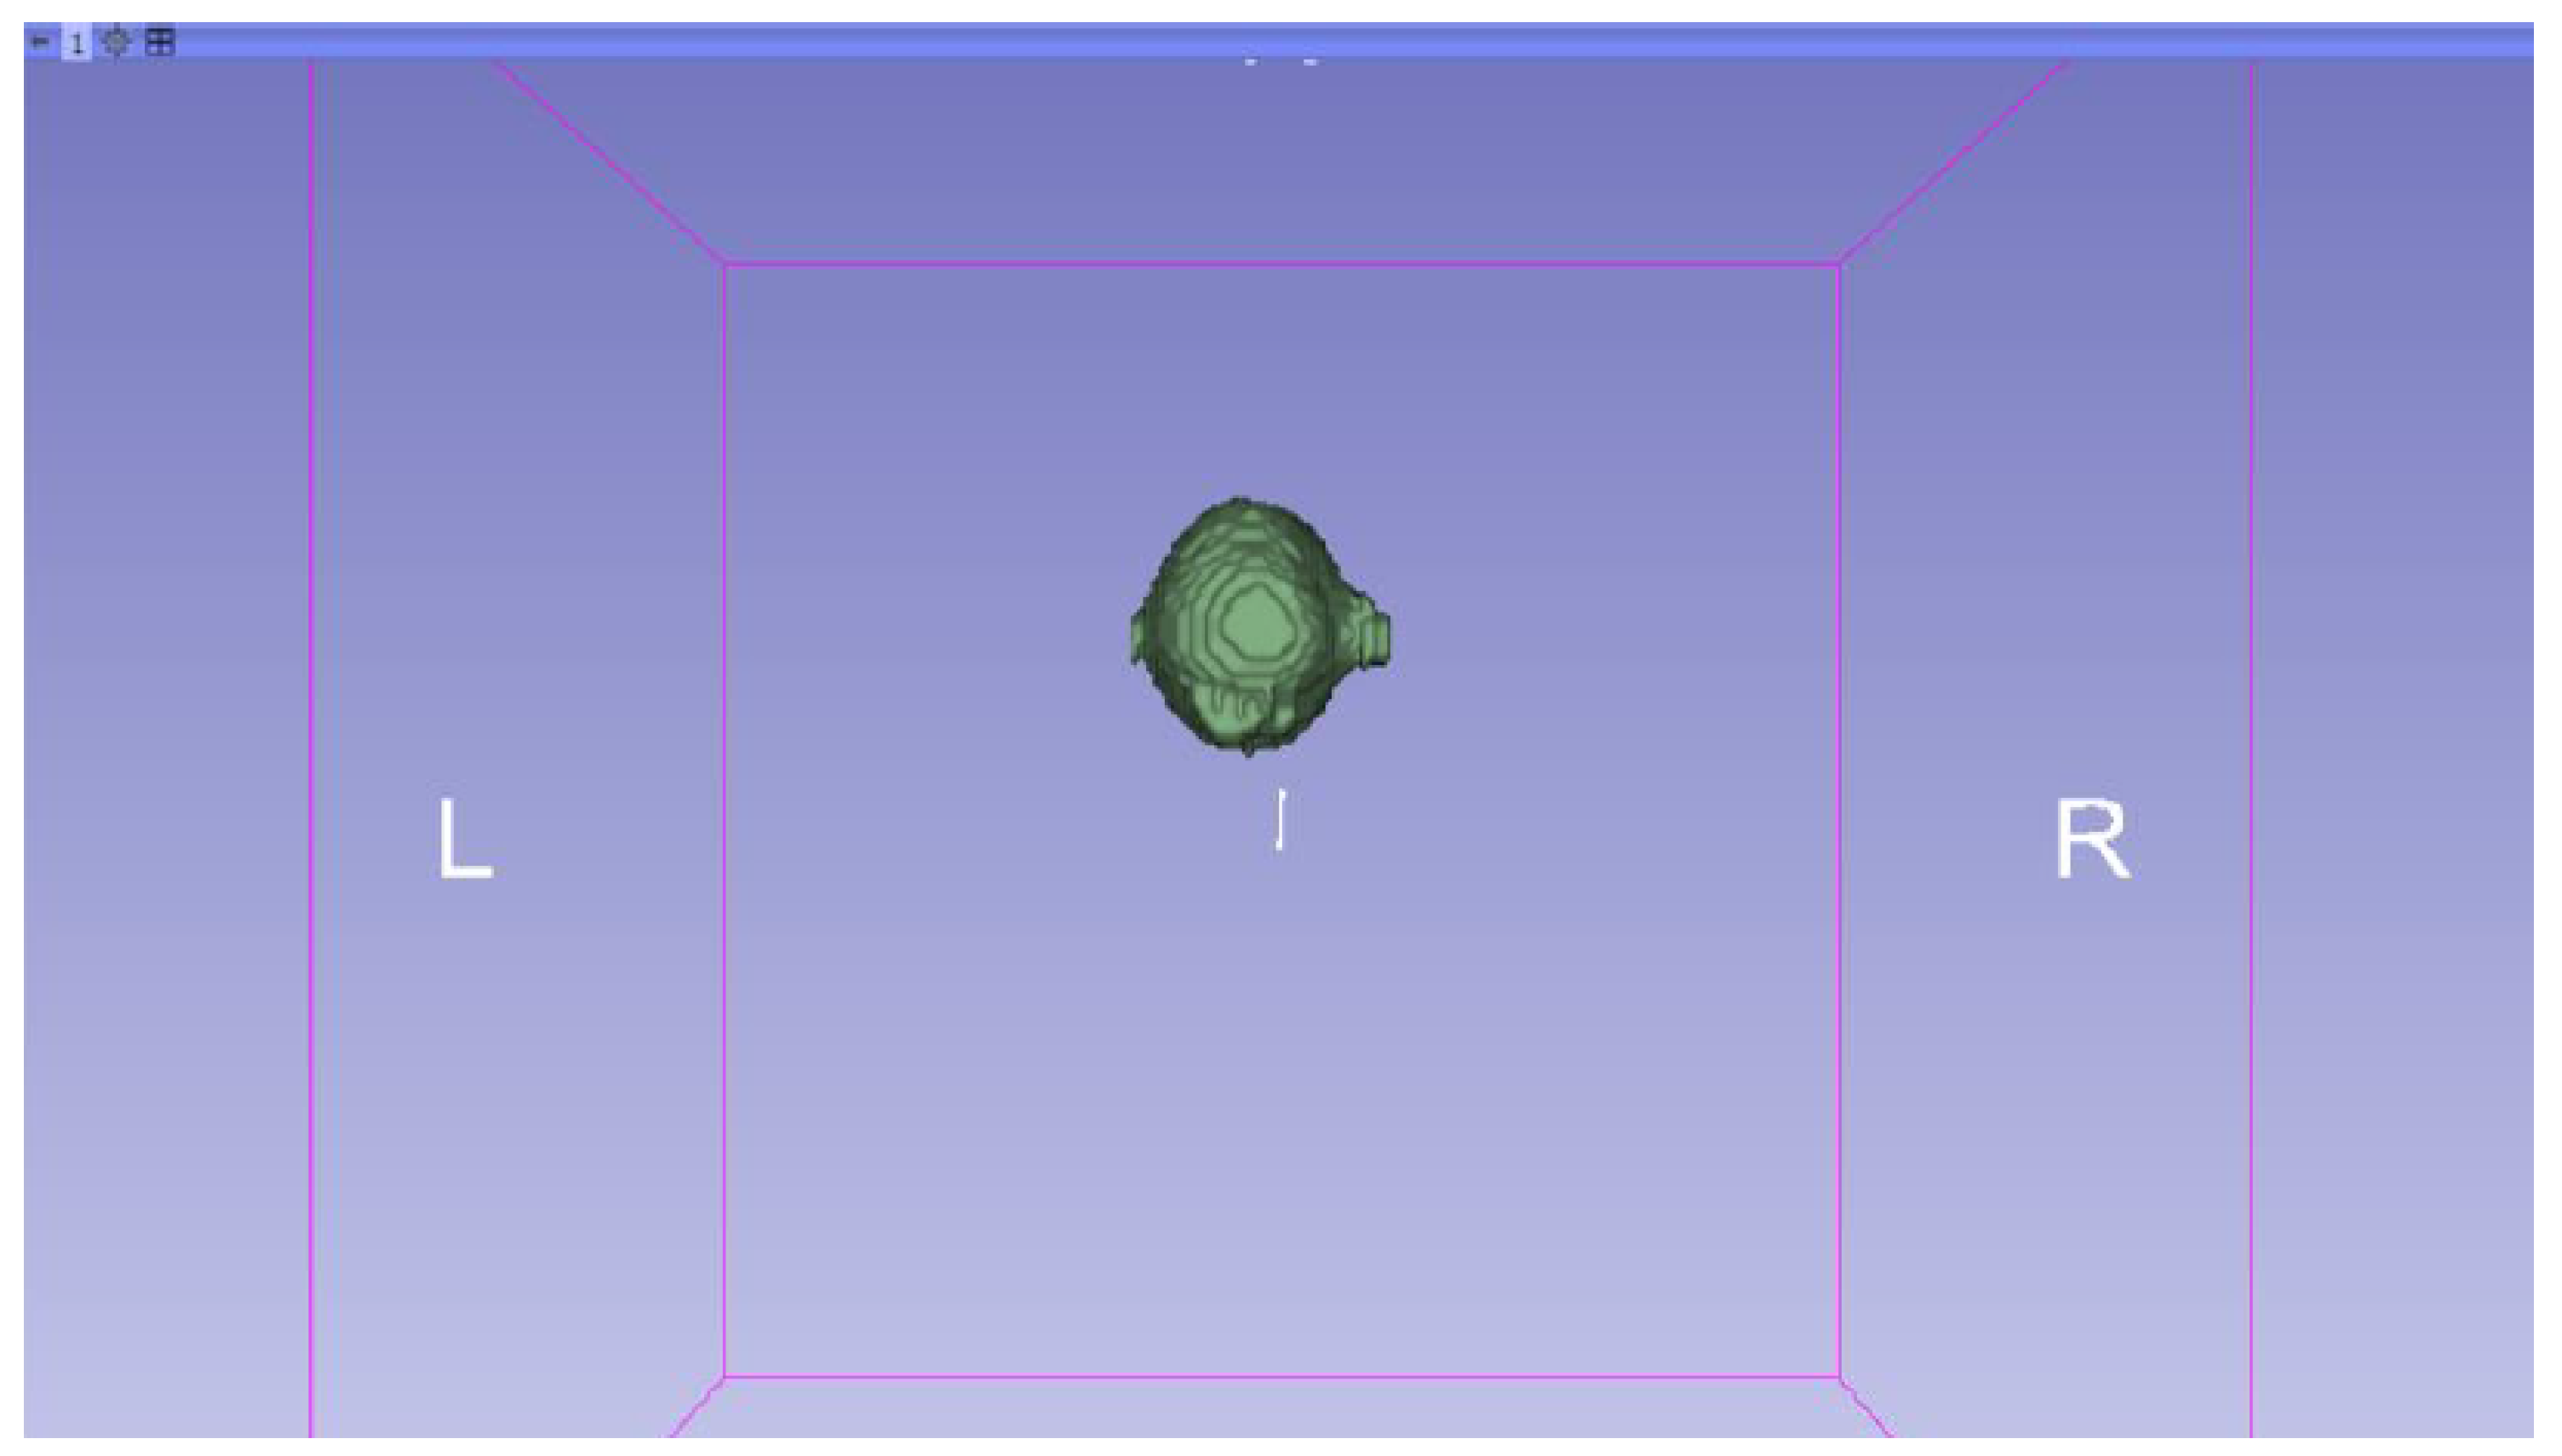

3.3. Human Brain Tumour

3.3.1. DICOM-to-STL Files

- Go to the “Segmentations” Module in the toolbar.

- Go to “Export/import models and label maps”.

- In the menu, select “model” as the output option.

- In “Export to files”, choose the destination folder.

- Select the STL file format, and, finally, click on “Export”.